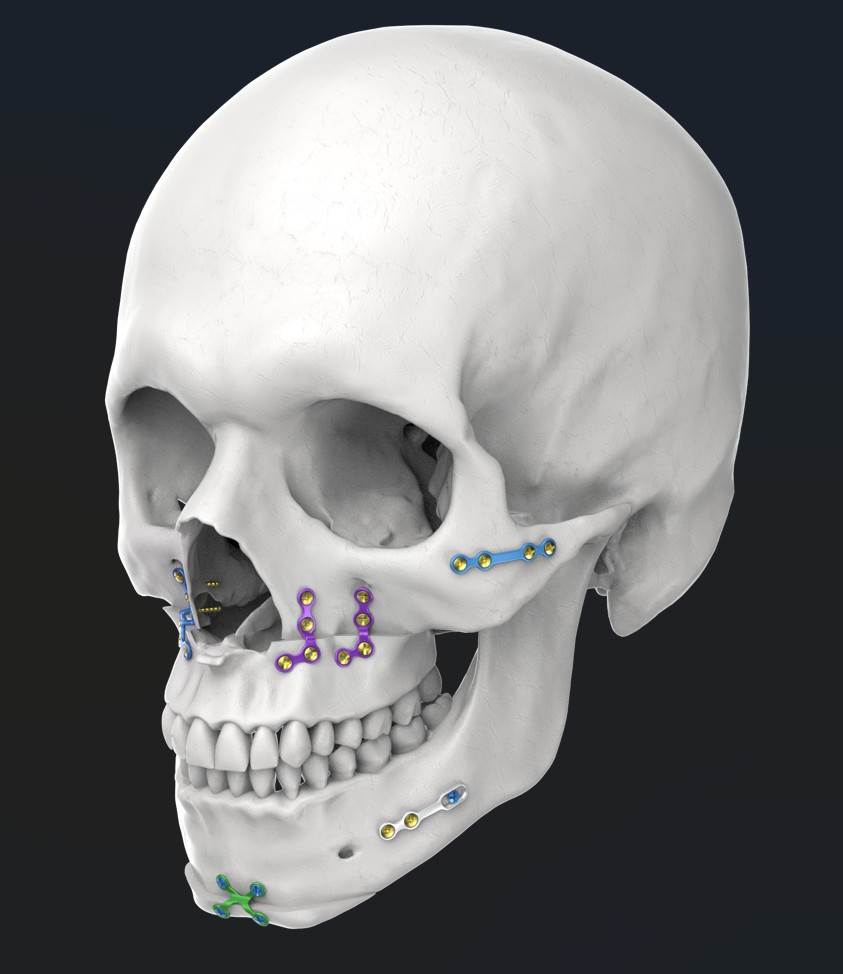

La cirugía ortognática consiste en realizar osteotomías (cortes en el hueso) en los maxilares para poder movilizarlos en la posición planificada. La nueva posición se fijará mediante miniplacas y/o tornillo de titanio para mantener su posición.

- Planificación virtual de la cirugía con la ayuda de un software específico que integra los registros digitales tomados al paciente (escaneado 3D de los dientes, tomografía computarizada de los maxilares y registros fotográficos) con el fin de fabricar unas guías (férulas quirúrgicas) que ayudarán al cirujano a posicionar correctamente los segmentos óseos.